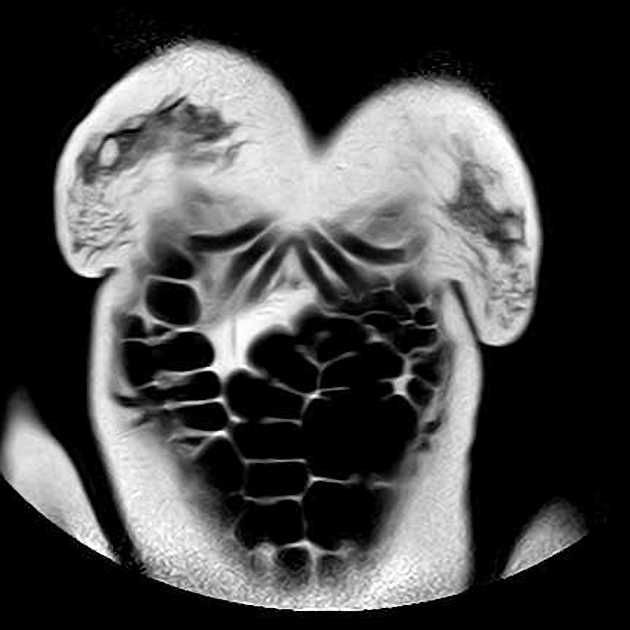

- Nhiều nang thận đơn thuần cũng như nhiều u thận tổn thương hỗn hợp đặc - nang.

Ca lâm sàng này biểu hiện đầy đủ các đặc điểm của hội chứng Von Hippel-Lindau (VHL), bao gồm nhiều nang thận đơn thuần và nhiều u thận tổn thương hỗn hợp đặc - nang. Tuyến tụy cũng có rất nhiều nang lan tỏa.

Bệnh nhân đã từng được phẫu thuật cắt bỏ u mạch thần kinh đệm (hemangioblastoma) ở tủy sống, gây ra tình trạng bàng quang thần kinh (lưu ý hình ảnh cắt lớp ngang T2 cho thấy dấu hiệu của phẫu thuật cắt mảnh cung (laminectomy) vùng ngực và các thay đổi tại tủy sống).